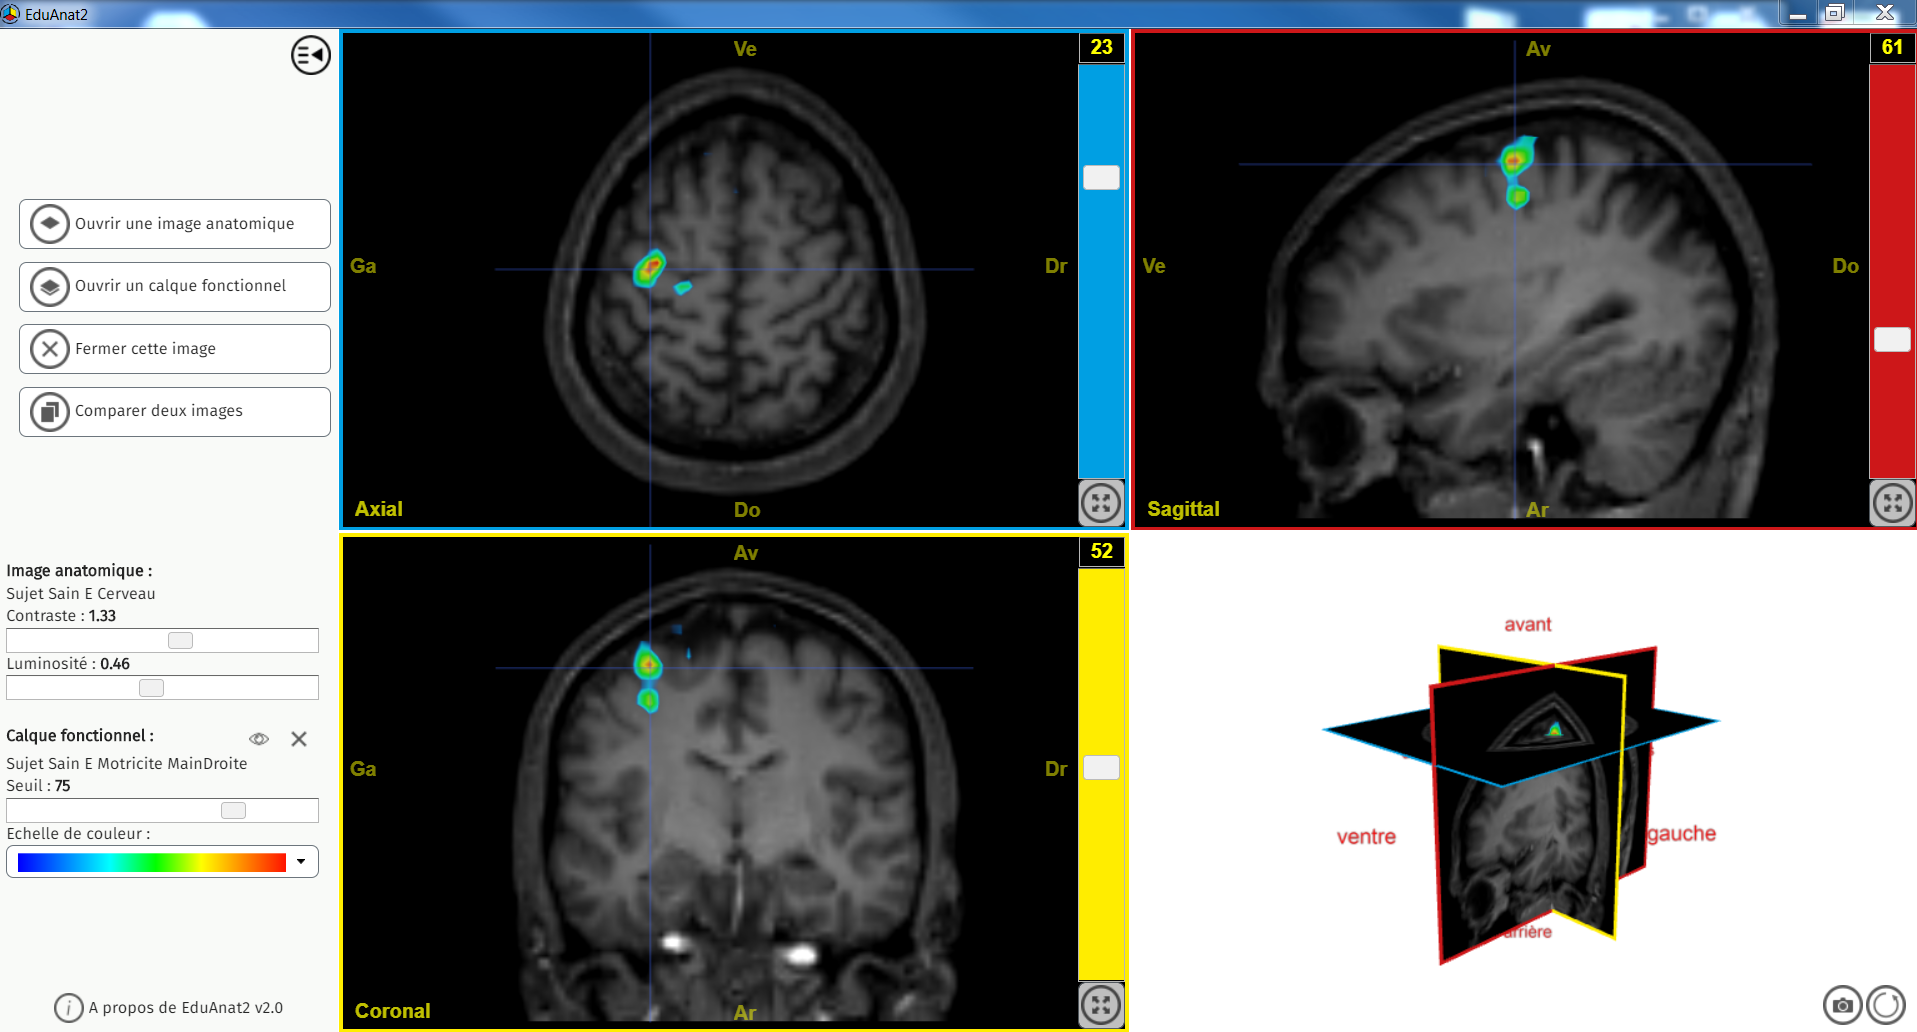

E motricité main droite